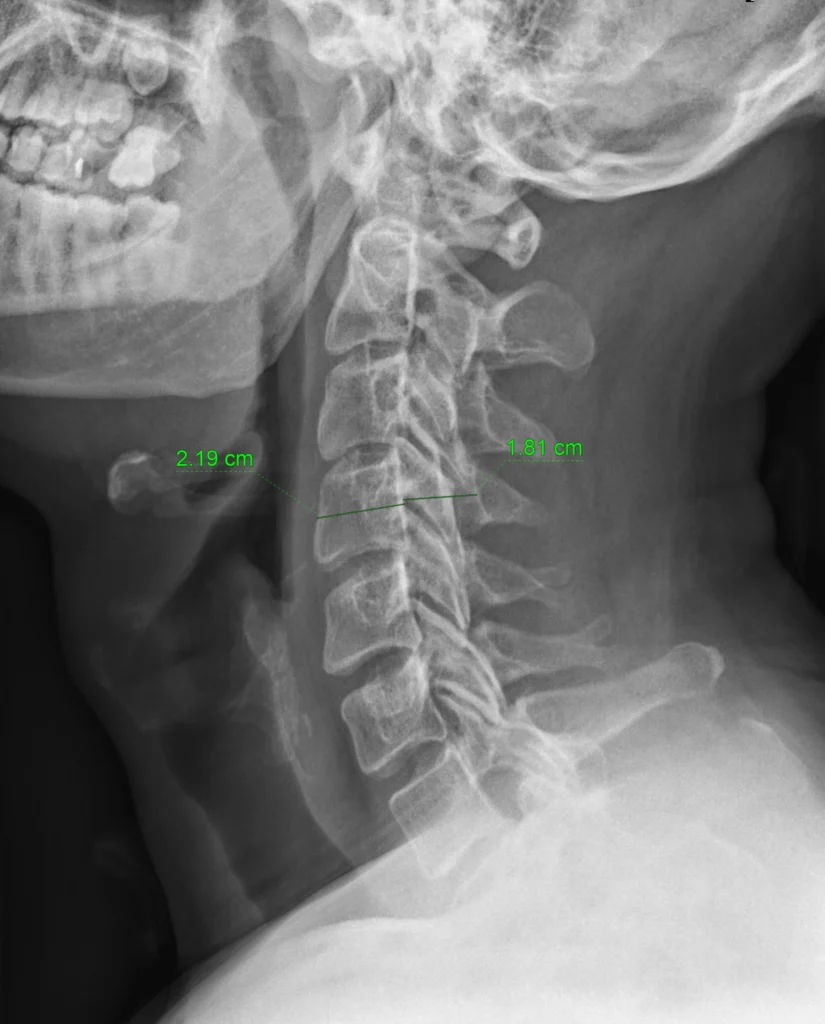

Imagen anotada

El índice de Pavlov y Torg es la relación entre el diámetro del canal cervical y el ancho del cuerpo vertebral cervical al mismo nivel en una radiografía lateral de la columna cervical. En este ejemplo: 1.81 / 2.19 = 0.82